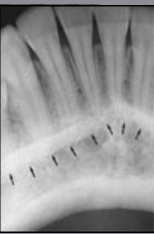

what type

HBL